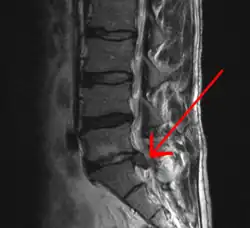

![]() Imagen por resonancia magnética que muestra una hernia discal | ||

La hernia discal es una enfermedad en la que parte del disco intervertebral (núcleo pulposo), que se encuentra entre las vértebras, se desplaza hacia la raíz nerviosa, la presiona y produce lesiones neurológicas derivadas de esta lesión. Pueden ser contenidas (solo deformación, también llamada protrusión discal) o con rotura.